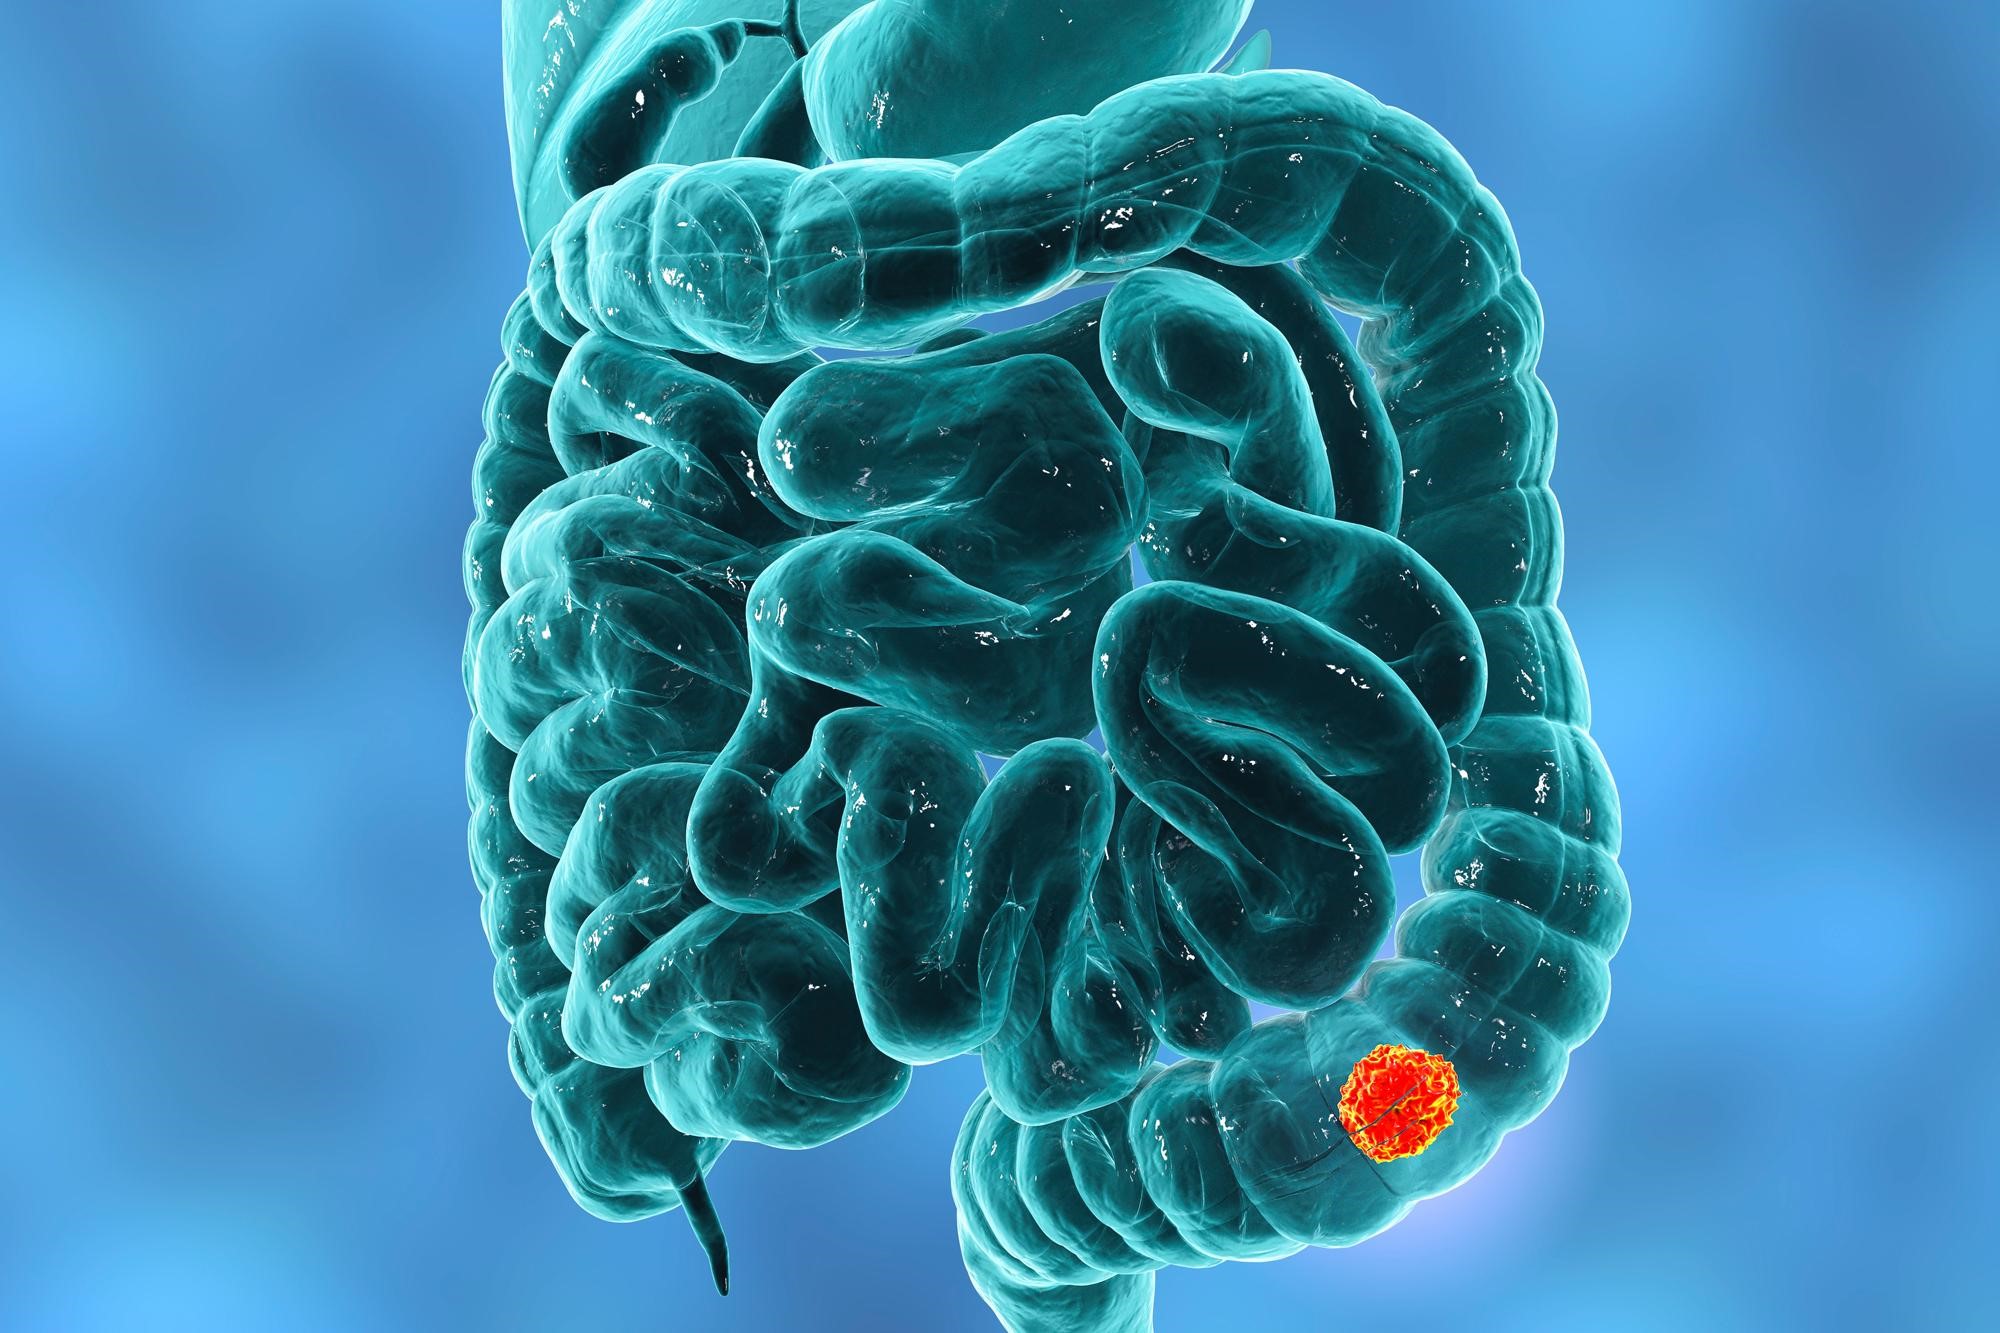

Ερευνητές ανακάλυψαν μια δραματική αύξηση στα περιστατικά καρκίνου του παχέος εντέρου, ιδιαίτερα μεταξύ παιδιών και εφήβων στις ΗΠΑ.

Από το 1999 έως το 2020, τα ποσοστά καρκίνου του παχέος εντέρου αυξήθηκαν κατά 500% σε παιδιά ηλικίας 10-14 ετών, κατά 333% σε έφηβους 15-19 ετών και κατά 185% σε νέους ενήλικες 20-24 ετών.

Το 2020, 0,6 παιδιά ηλικίας 10-14 ετών ανά 100.000 πληθυσμού διαγνώστηκαν με καρκίνο του παχέος εντέρου, σε σύγκριση με 0,1 ανά 100.000 το 1999. Οι διαγνώσεις στους έφηβους 15-19 ετών αυξήθηκαν από 0,3 σε 1,3 ανά 100.000 και στους νέους ενήλικες 20-24 ετών από 0,7 σε 2 ανά 100.000.

Επιπλέον, διαπιστώθηκε αύξηση και σε μεγαλύτερες ηλικίες, με τα ποσοστά να αυξάνονται κατά 71% στις ηλικίες 30-34 ετών, κατά 58% στις ηλικίες 35-39 ετών και κατά 37% στις ηλικίες 40-44 ετών.

Η ηλικιακή ομάδα 40-44 ετών είχε τη μικρότερη ποσοστιαία αύξηση, αλλά το υψηλότερο ποσοστό εμφάνισης καρκίνου του παχέος εντέρου, φθάνοντας τα 20 περιστατικά ανά 100.000 άτομα το 2020.